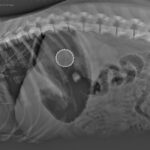

Gastroscopia per estrazione corpo estraneo

A volte, giocando, i nostri animali deglutiscono gli oggetti più svariati (denominati corpi estranei).

Questi possono per dimensioni e peso rimanere nello stomaco anche parecchio tempo.

Nelle foto un tappo di birra, rimasto per 10 gg nello stomaco di un cucciolo di 4 mesi, come visualizzato alla radiografia e, successivamente in gastroscopia, procedura che ne ha permesso l’asportazione in modalità non invasiva.